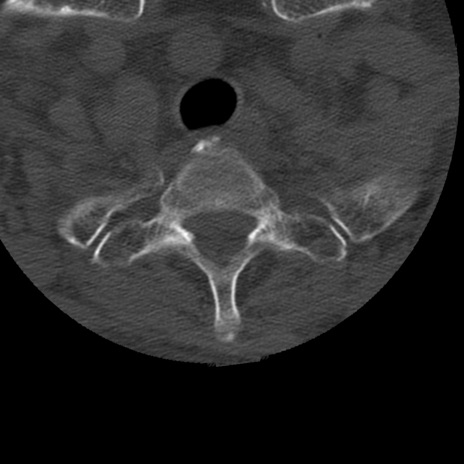

症例50 頚椎CT(横断像)

頚椎CT